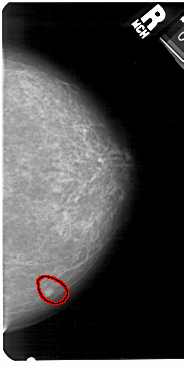

A_1418_1.RIGHT_MLO

LEFT_MLO LINES 5491 PIXELS_PER_LINE 3256 BITS_PER_PIXEL 12 RESOLUTION 43.5 NON_OVERLAY

FILE: A_1418_1.RIGHT_MLO.OVERLAY

TOTAL_ABNORMALITIES 1

ABNORMALITY 1

LESION_TYPE MASS SHAPE LOBULATED MARGINS CIRCUMSCRIBED

ASSESSMENT 4

SUBTLETY 4

PATHOLOGY BENIGN

TOTAL_OUTLINES 1

BOUNDARY